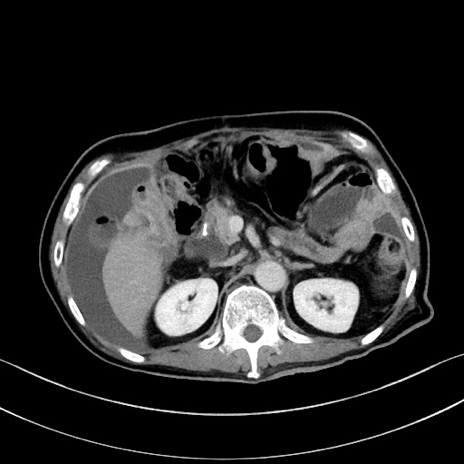

症例28(横断像)

【症例】60歳代男性

【主訴】嘔吐

【現病歴】胃癌にて胃全摘後。食思不振が悪化し、夜中に嘔吐することがある。

【既往歴】胃癌、胃全摘、脾摘、胆摘後

【データ】WBC 5900、CRP 10.56